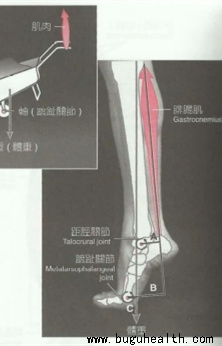

- 布骨医学科普:小腿三头肌的知识你知道多少? BuGuRMC布骨康复医疗中心 ,2023-01-30

- 今天就小腿三头肌进行简单的介绍。首先小腿被誉为“第二心脏”,在我们膝关节术后早期常常利用“踝泵”,也就是踝关节的主动背屈和跖屈,来促进下肢的循环以消除肿胀,但是在恢复至中后期时,很多人可能会忽略掉小腿三头肌的练习,但根据Burdett的数学模型结果,跑步时跟腱可以承受相当于体重5.3-10倍的力。.....